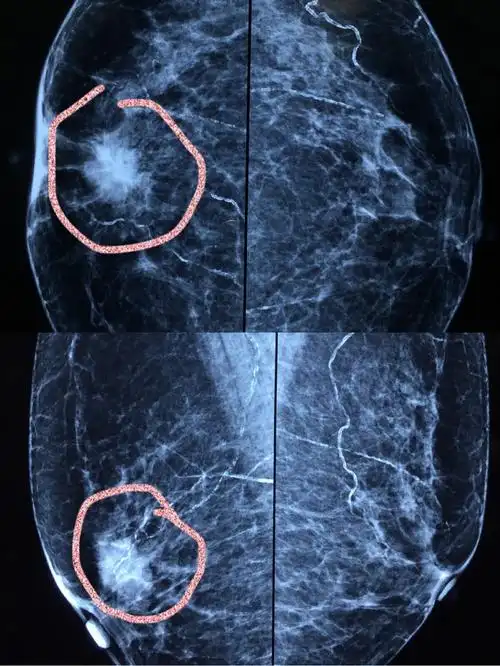

许多乳腺癌患者通过自己发现或常规体检,或乳腺x摄片发现肿块.

因发现右乳肿块一月入院,术前钼靶及彩色b超均呈典型的乳腺癌表现

早期乳腺癌的常见表现:无痛单个小肿块,局部隆起,酒窝征